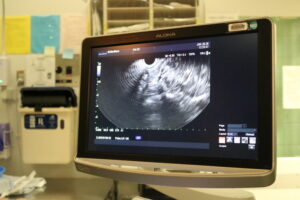

Quatre nouveaux instruments réutilisables appelés échographes endoscopiques, qui ont été acquis grâce aux dons faits à la Fondation, ont été largement utilisés dans l’unité d’endoscopie en septembre 2025.

« L’endoscopie traditionnelle consiste à insérer une caméra fixée à un long tube fin et souple dans les intestins. Habituellement, nous examinons l’œsophage et l’estomac, ou bien le côlon et le rectum », explique le Dr Moffatt. « Grâce à ces échographes endoscopiques, nous pouvons bien sûr examiner l’intérieur des intestins, mais ils sont également équipés d’une sonde à ultrasons à leur extrémité, qui nous permet de voir à travers les parois intestinales et d’observer les organes adjacents », poursuit-il.

« Nous pouvons donc examiner le pancréas depuis l’estomac. Ou examiner la prostate et les autres organes pelviens depuis le rectum. Cela nous permet d’examiner plus en profondeur les parois intestinales afin de déterminer le stade du cancer ou d’observer entre les couches », ajoute-t-il, en expliquant qu’avant l’échographe endoscopique, il devait souvent recourir à des examens complémentaires, notamment par IRM ou tomodensitométrie, ce qui obligeait les patients à faire des allers-retours entre les services.

L’échographe endoscopique permet également aux médecins de prélever des biopsies à l’aide d’une aiguille fine. « Nous pouvons aller dans le pancréas ou dans le foie pour faire des biopsies, ce qui est impossible avec une sonde classique. Et c’est important : cela permet un diagnostic plus rapide et plus précis des cancers », explique-t-il.